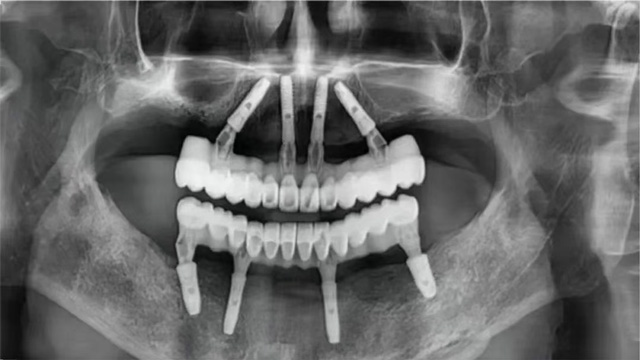

全口種植手術(shù)完成后,張先生感覺(jué)不錯(cuò)。稍事休息后完成了即刻修復(fù),戴上了臨時(shí)牙冠。幾個(gè)月后,張先生回院復(fù)診,戴上了正式牙冠??粗R子里一排整齊又漂亮的牙齒,他露出了久違的笑容。

全口無(wú)牙頜即拔即種術(shù)后全景片

10年后,他慶幸自己選擇了新橋口腔這樣的醫(yī)療機(jī)構(gòu),慶幸遇到姜辰主任樣有技術(shù)、有經(jīng)驗(yàn)的醫(yī)生,通過(guò)種植8顆種植體恢復(fù)了全口咀嚼功能,讓他在晚年得以重拾口福。

張先生重獲24顆牙